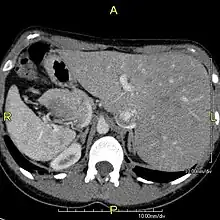

However, in some individuals with PCD, mutations thought to be in the gene coding for the key structural protein left-right dynein (lrd)[4] result in monocilia which do not rotate. There is therefore no flow generated in the node, Shh moves at random within it, and 50% of those affected develop situs inversus, which can occur with or without dextrocardia, where the laterality of the internal organs is the mirror-image of normal. Affected individuals therefore have Kartagener syndrome. This is not the case with some PCD-related genetic mutations: at least 6% of the PCD population have a condition called situs ambiguus or heterotaxy, where organ placement or development is neither typical (situs solitus) nor totally reversed (situs inversus totalis) but is a hybrid of the two.[6] Splenic abnormalities such as polysplenia, asplenia and complex congenital heart defects are more common in individuals with situs ambiguus and PCD, as they are in all individuals with situs ambiguus.[18]

When accompanied by the combination of situs inversus (reversal of the internal organs), chronic sinusitis, and bronchiectasis, it is known as Kartagener syndrome[3] (only 50% of primary ciliary dyskinesia cases include situs inversus).[11]